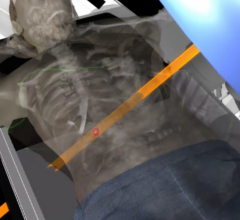

The radiation therapy channel covers all aspects of radiation oncology technology. Radiation therapy includes linear accelerators (LINAC), proton therapy, brachytherapy, image guided radiation therapy (IGRT), focused ultrasound, stereotactic body radiation therapy (SBRT), intensity modulated radiation therapy (IMRT), treatment planning systems and tomotherapy.

Automation is transforming the way we practice radiation oncology and advancing the standard of patient care. There have ...

Treating cancer effectively often includes a combination of patient therapies. In recent years, technology advancements ...